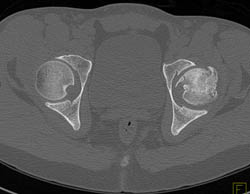

Arteriovenous Malformation (AVM) Shoulder With Embolization